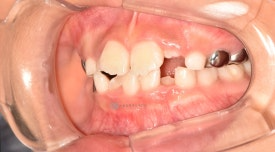

치료 전 - 위아래 심한 공간 부족이 관찰됩니다.

자세히 보면 아래 영구치 어금니의 충치도 치료하는 과정에서 깨끗하게 레진치료 해주었습니다. 교정하면서 충치검진이나 치료를 위해 다른 치과에 내원하지 않아도 된다는 점이 바쁜 우리 아이들에게는 큰 장점으로 다가오는 것 같습니다. 서울효앤주니어치과에서 교정체크 = 충치검진

치료 전 - 위아래 심한 공간 부족이 관찰됩니다.자세히 보면 아래 영구치 어금니의 충치도 치료하는 과정에서 깨끗하게 레진치료 해주었습니다. 교정하면서 충치검진이나 치료를 위해 다른 치과에 내원하지 않아도 된다는 점이 바쁜 우리 아이들에게는 큰 장점으로 다가오는 것 같습니다. 서울효앤주니어치과에서 교정체크 = 충치검진